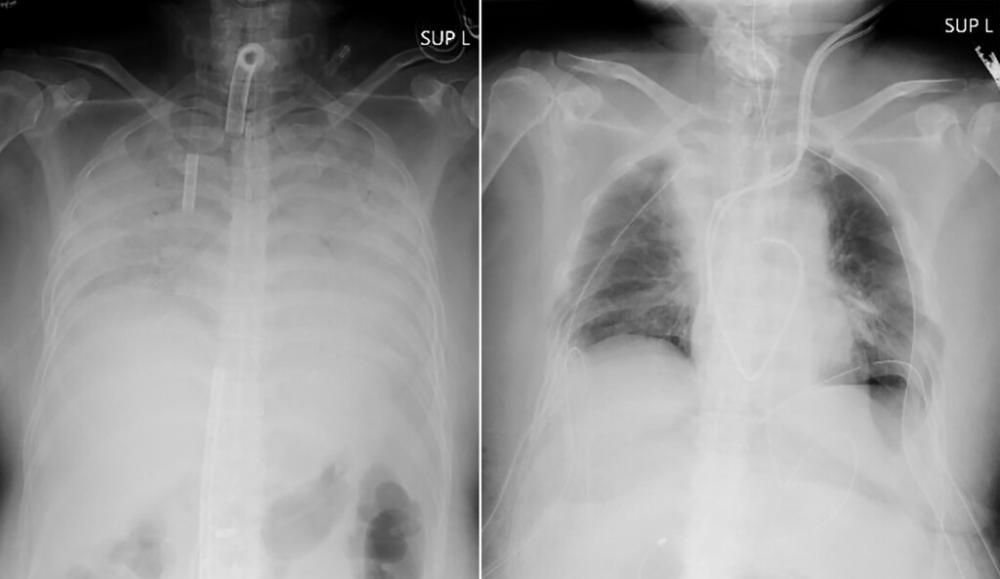

The woman contracted COVID-19 late last year and developed breathing difficulties that rapidly worsened. She was placed on a life support machine that works as an artificial lung for more than three months at another hospital because her lungs were so severely damaged.

Even after she was free of the virus, her lungs were no longer functional or treatable, and the only option for her to live was to receive a lung transplant, the university said.